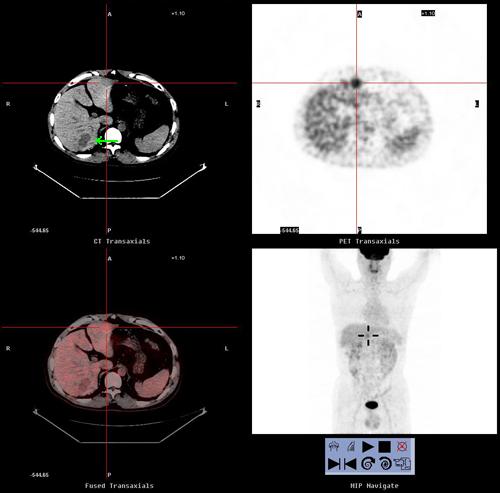

pet/ct体检发现小肝癌病灶

红色十字线处为肿瘤病灶,绿色箭头处为囊肿 病理结果为高分化肝细胞癌

图解petct